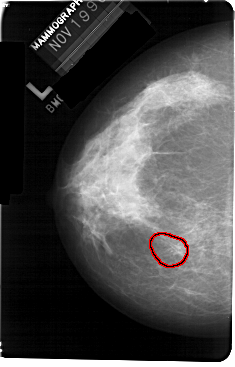

A_1301_1.LEFT_MLO

LEFT_MLO LINES 5491 PIXELS_PER_LINE 3601 BITS_PER_PIXEL 12 RESOLUTION 43.5 OVERLAY

FILE: A_1301_1.LEFT_MLO.OVERLAY

TOTAL_ABNORMALITIES 1

ABNORMALITY 1

LESION_TYPE CALCIFICATION TYPE PLEOMORPHIC DISTRIBUTION CLUSTERED

ASSESSMENT 4

SUBTLETY 2

PATHOLOGY BENIGN

TOTAL_OUTLINES 1

BOUNDARY